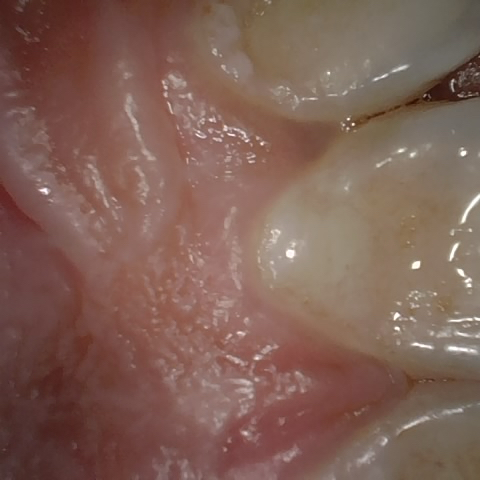

Incorrect Quality Level

The reference annotation for this image is

None

.

Please select the correct quality level.

Annotated as "Good"